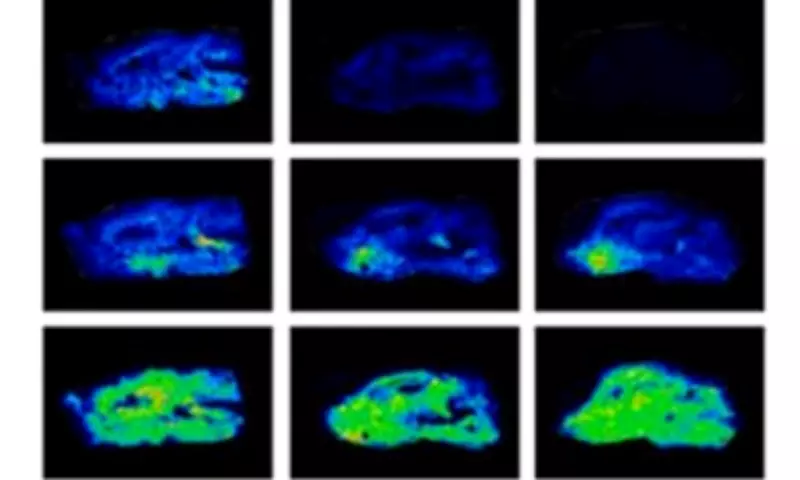

Researchers conducted controlled experiments comparing mice given oral flavanol doses with those receiving only water. Analysis revealed the flavanol-consuming group demonstrated significantly stronger performance in learning and memory tasks, despite minimal absorption into their bodies.

The study, published in Current Research in Food Science, documented that flavanols boosted neurotransmitter activity across multiple brain regions. Shortly after administration, levels of dopamine (the 'feel-good' hormone) and norepinephrine (the 'fight-or-flight' hormone) increased substantially.

The researchers concluded that flavanols function as moderate stressors stimulating the central nervous system, leading to enhanced attention, alertness, and memory capacity. Rather than working primarily through bloodstream absorption, they trigger broad physiological responses comparable to those produced by physical exercise.

The research team noted: 'The series of experiments revealed that a single oral administration of flavanols had a marked impact on neurotransmitter dynamics throughout the brain. These insights suggest that the sensory properties of food are important for promoting human health.'